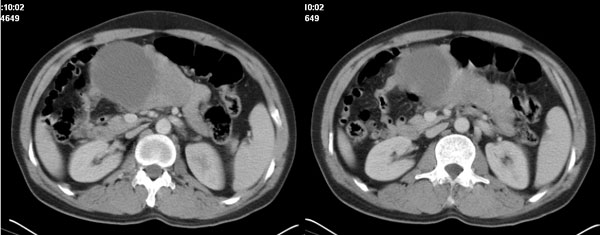

李**,男,46岁,便血1天入院,慢性贫血貌,腹平、软,剑突下压痛,肠鸣音稍活跃,hb大于1g/l,胃镜:慢性浅表性胃炎,b超:1肝内多发性占位 2腹腔内囊性肿块 ,肝内圆形影平扫ct值42.9,动脉期48.6,静脉期58.2,延迟期62.2

影像学表现:1 腹腔前中部、胰腺前方囊实性病灶(个人认为确定有否实性成分存在这是关键,涉及到鉴别诊断,如果是口服阳性造影剂则可明确左侧是不是小肠了),囊性部分囊壁不均,实性部分有强化,与小肠关系较密切,局部小肠受推移;与胰头、胃后壁均有脂肪间隙存在;2 胰腺无异常改变,胰周无渗出;3肝后段包膜下2个小圆形低密度灶,从图像和楼主提供的ct值来看有轻度强化,灶周无片状强化,不似单纯囊肿及肝癌、炎性病变表现;4 腹膜后及腹腔内无淋巴结肿大。

胰腺边界清晰,胰周筋膜不厚,胰周脂肪密度无明显增高;其前方囊实性病灶,边界清晰,增强后实性部分轻度强化;肝内多发边界清晰低密度影,增强后无明显强化(平扫ct值42.9,动脉期48.6,静脉期58.2,延迟期62.2)。